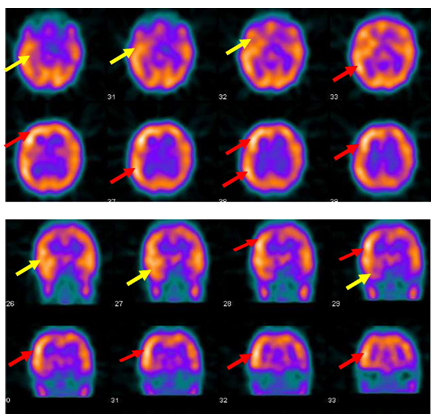

A twelve years old right handed boy a school student referred to the epilepsy monitoring unit for epilepsy surgery evaluation of pharmaco-resistant epilepsy that failed several antiepileptic drugs monotherapy and poly therapy trials. The patient is a product of full term normal spontaneous vaginal delivery with normal mile stones. He had febrile convulsions at the age of one year with no recurrence and had family history of epilepsy with one sibling and one paternal cousin had epilepsy with generalized tonic clonic seizures in remission on anti epileptic drugs. The first generalized tonic clonic seizure occurred at the age of seven years preceded by an aura of rising abdominal pain and followed by post ictal fatigue. Generalized tonic clonic seizures recurred at weekly interval with and without the preceding abdominal pain. At times the abdominal pain occurs with no generalized tonic clonic seizures but followed by lack of concentration and fatigue. The seizures occurred mainly during wakefulness but could occur during sleep. The patient never achieved seizure remission and never developed status epilepticus despite frequent seizures. He was admitted to the epilepsy monitoring unit EMU at the age of twelve years. He was on two antiepileptic drugs namely topiramate one hundred milligram twice daily and lamotrigine two hundred milligram twice daily with almost weekly seizures. His neurological, general and systemic examinations were normal. The patient was kept on his antiepileptic drugs and had five days video electroencephalography EEG monitoring using ten-twenty system scalp EEG electrodes with additional anterior temporal electrodes T1 electrode on the left anterior temporal region and T2 electrode on the right anterior temporal region respectively. During the video EEG monitoring the patient developed four stereotyped electroclinical seizures. Three were during wakefulness and one during sleep. No generalized tonic clonic seizures recorded. The seizures were preceded by abdominal pain in one seizure only. The seizure semiology starts with abrupt asymmetric abduction of both upper and lower limbs with prominent tonic and dystonic contraction of the left upper and lower limbs and adversive eyes and head deviation to the left with proximal automatic movements of the right arm and leg. The duration of seizure was fifty to sixty seconds during which the patient was unresponsive with early recovery of comprehension and speech in the post ictal phase. The ictal EEG onset starts with right frontal regional suppression followed by slow activity of the right hemisphere in all recorded seizures. The interictal EEG showed asymmetric background with excessive slow transients of three to five hertz activity in the right hemisphere with frequent repetitive interictal spikes and polyspike-wave discharges at right frontopolar region intermixed with two to three slow transients (Figure 1). The electroclinical seizures recorded favored right hemispheric epilepsy with early engagement of the right frontal regions. Preadmission MRI of the brain showed right hippocampal sclerosis HS. Ictal single-photon emission computed tomography SPECT with technetium-99m hexamethyl-propylene amine oxime Tc-99m HMPAO injected at twenty five seconds after ictal EEG onset of the fourth seizure showed right medial and lateral temporal lobe hyperpefusion (Figure 2). Interictal positron emission tomography with F-18 fluorodeoxyglucose F-18 FDG-PET showed right hemisphere hypometabolism with marked reduction of F-18-FDG metabolism at right frontal, right temporal, right parietal and right thalamic regions (Figure 3). As the initial MRI diagnosis of right HS could not alone explain the seizures of the patient with a high probability of additional right hemispheric neocortical focus a follow up high resolution three Tesla MRI brain was performed prior to invasive EEG recording. The MRI brain clearly demonstrated right temporal pole cortical dysplasia in addition to the right HS (Figure 4).The diagnosis of dual pathology was made with right temporal pole cortical dysplasia and right HS the so called HS+. The patient underwent directly epilepsy surgery without invasive EEG implantation .He received extensive right temporal lobectomy under intraoperative electrocorticography and regions with active spiking were removed (Figure 5). Histopathology of the resected right hippocampus showed HS and tissue from the right temporal pole confirmed the presence of focal cortical dysplasia type III. The patient had no post surgical complications. The patient became seizure free and six month post epilepsy surgery interictal EEG was normal. Currently the patient is seizure free with significant cognitive improvement at five years post epilepsy surgery on lamotrigine 25mg once daily .He attends high school and plans to be a teacher.

Figure 2 Ictal SPECT with Tc-99m HMPAO injected at twenty five seconds after ictal EEG onset of the fourth seizure shows right medial and lateral temporal lobe hyperpefusion (yellow arrows) and right frontal and right parietal hyperperfusion ( red arrows).